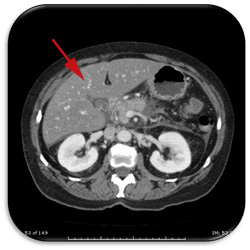

A demonstração do acúmulo de gordura geralmente é realizada através de exames complementares de imagem (ecografia, tomografia computadorizada ou ressonância nuclear magnética). Estes exames são considerados geralmente suficientes para o diagnóstico da esteatose, podendo também informar se há sinais de desenvolvimento de cirrose ou de hipertensão portal. Mas não permitem a diferenciação entre a esteatose e a esteato-hepatite nem diferenciar graus intermediários de fibrose ou de atividade da inflamação. É possível diferenciar grosseiramente o acúmulo de gordura entre leve (grau I), moderada (grau II) e severa (grau III), embora isso tenha pouca utilidade clínica.

No entanto os exames de imagem, especialmente a ultrassonografia, podem errar o diagnóstico. Doenças como a hemocromatose (onde há acúmulo de ferro no fígado) e glicogenoses (acúmulo de metabólitos de glicogênio) podem ser muito semelhantes à esteatose. Assim, considera-se que o melhor exame para o diagnóstico da esteatose é a biópsia hepática com análise histopatológica do material coletado. Além de confirmar a presença do acúmulo de gordura e diferenciar de outras doenças, permite avaliar se há hepatite e o quanto a doença está avançada em termos de fibrose.